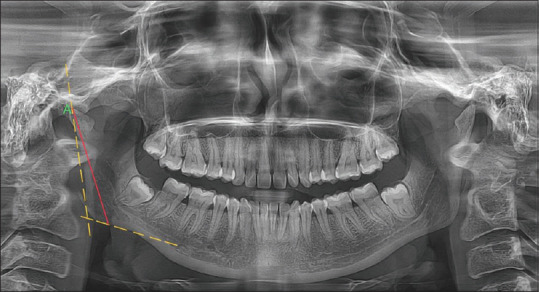

Materials and methods: A total of 200 digital panoramic radiographs were collected, out of which 100 were males and 100 were females. The average age range of the samples was 20-40 years. Coronoid height and condylar height were measured using Planmeca Romexis Viewer Software version 2.9.2.R (Planmeca OY, Helsinki, Finland). Random forest and elastic net algorithms were employed in the study.